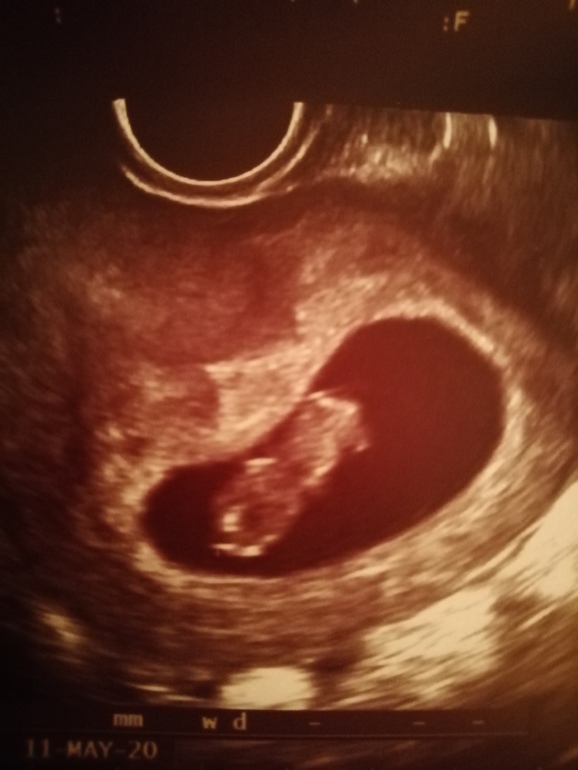

Всё о нашей беременностиДевчёнки сегодня была на узи срок ставят 9 недель как то они считают незнаю у меня меньше выходила..так вот

тамм человечек уже блин как же это волнительно🤩🤩🤪🤪от радости и про токсикоз забыла ,говорятвсе соотведствует норме ..ктр 21..мж 4.6...сб+170..хорион 40 ,как думаете размеры норм ??а то мало ли ...а так раслаблюсь на три недели до скрининга